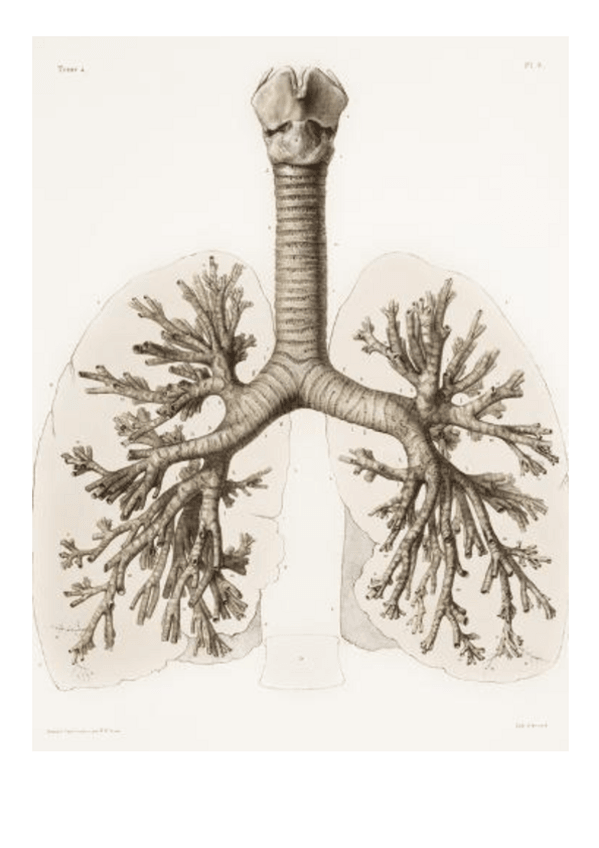

Tema-5Anatomia-de-la-traquea-y-del-arbol-bronquial.pdf

Tema-6Pulmones.pdf